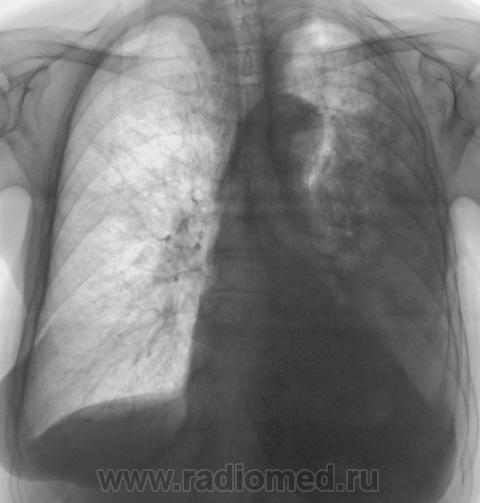

Контроль после флюорографии. Пациентка 3 года профилактическую флюорографию не проходила.

Калициноз плевры - возможно перенесенный туб. плеврит.

Подняли архив. Оказалось, что в 2008 г. пациентка лечилась в отделении по поводу пневмонии. После рентгенологического исследования "первичного", до лечения, настоятельно рентгенологом рекомендовалось провести рентген-контроль после лечения. Однако, на контроль пациентка направлена не была. Снимков нет, остались одни флюорограммы.